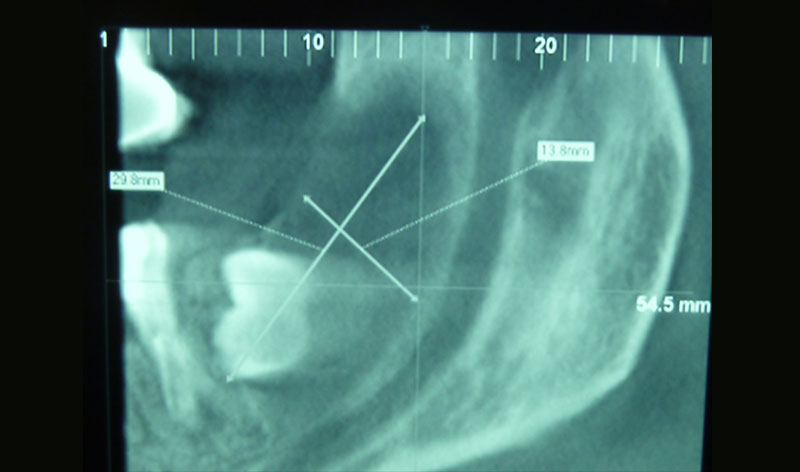

Dada su localización anatómica, en muchos casos el cordal se haya situado junto al nervio dentario, lo que aconseja un estudio radiológico preciso para situar con exactitud la relación entre cordal y nervio dentario.